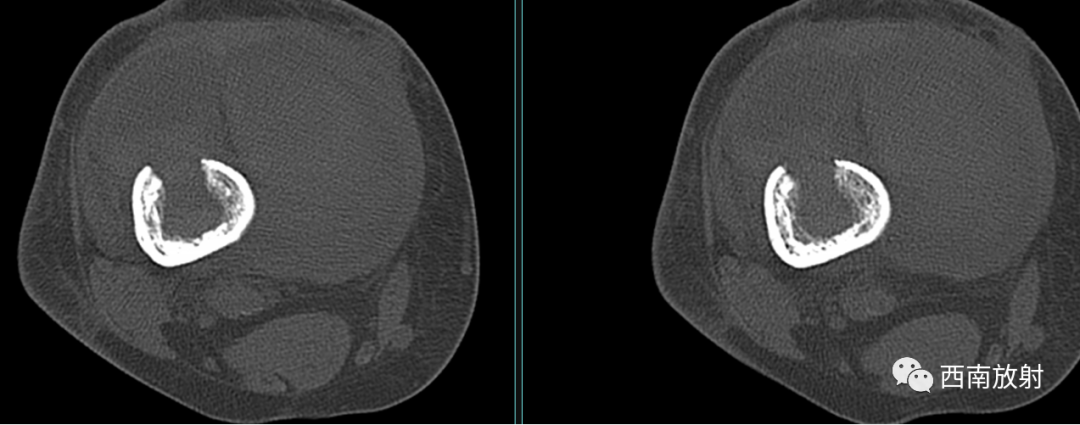

大体病理:右大腿中下段内侧骨膜外见一腔隙,约3X3X4cm,内有较多血凝块,有少许脓液,股骨下段周围有少许脓液,少量疤痕形成,右膝关节内有少许脓液,见有少许脓苔,右骨髓腔未见破坏,骨髓腔内有少许脓液,已被疤痕织包裹。

诊断:慢性骨髓炎,周围软组织脓肿。

CT显示骨破坏、脓肿、死骨及骨膜增生、骨质增生硬化,呈骨小梁密度增高、模糊,髓腔密度增大、狭窄,皮质增厚。MRI显示早期骨髓内广泛分布的斑片异常信号,与邻近正常骨髓信号相比较,T1WI信号减低,T2WI信号增高,脂肪抑制T2WI 或STIR 等序列上病变显示更清楚,骨皮质周围软组织内呈弥漫分布的T1WI低信号及T2WI高信号影,边界模糊。出现骨膜反应,骨皮质不规则破坏,脓肿及死骨形成。

▲软组织脓肿